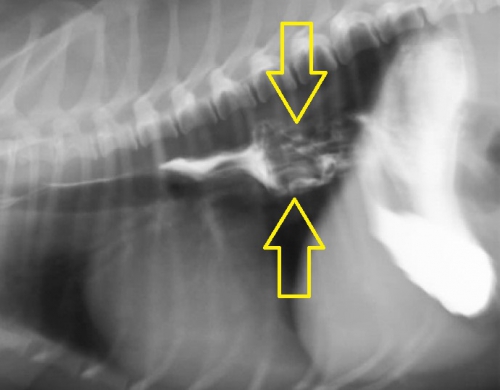

下が造影検査によって明らかになった胸部食道の異物の例です。上2枚の写真はリンゴ、下2枚は牛皮ガムが異物となっています。犬のおやつ類などは硬く、見た目に明らかな異物であっても撮影条件によっては意外にレントゲン写真に写りにくいため、診断する上で難しさを生じます。